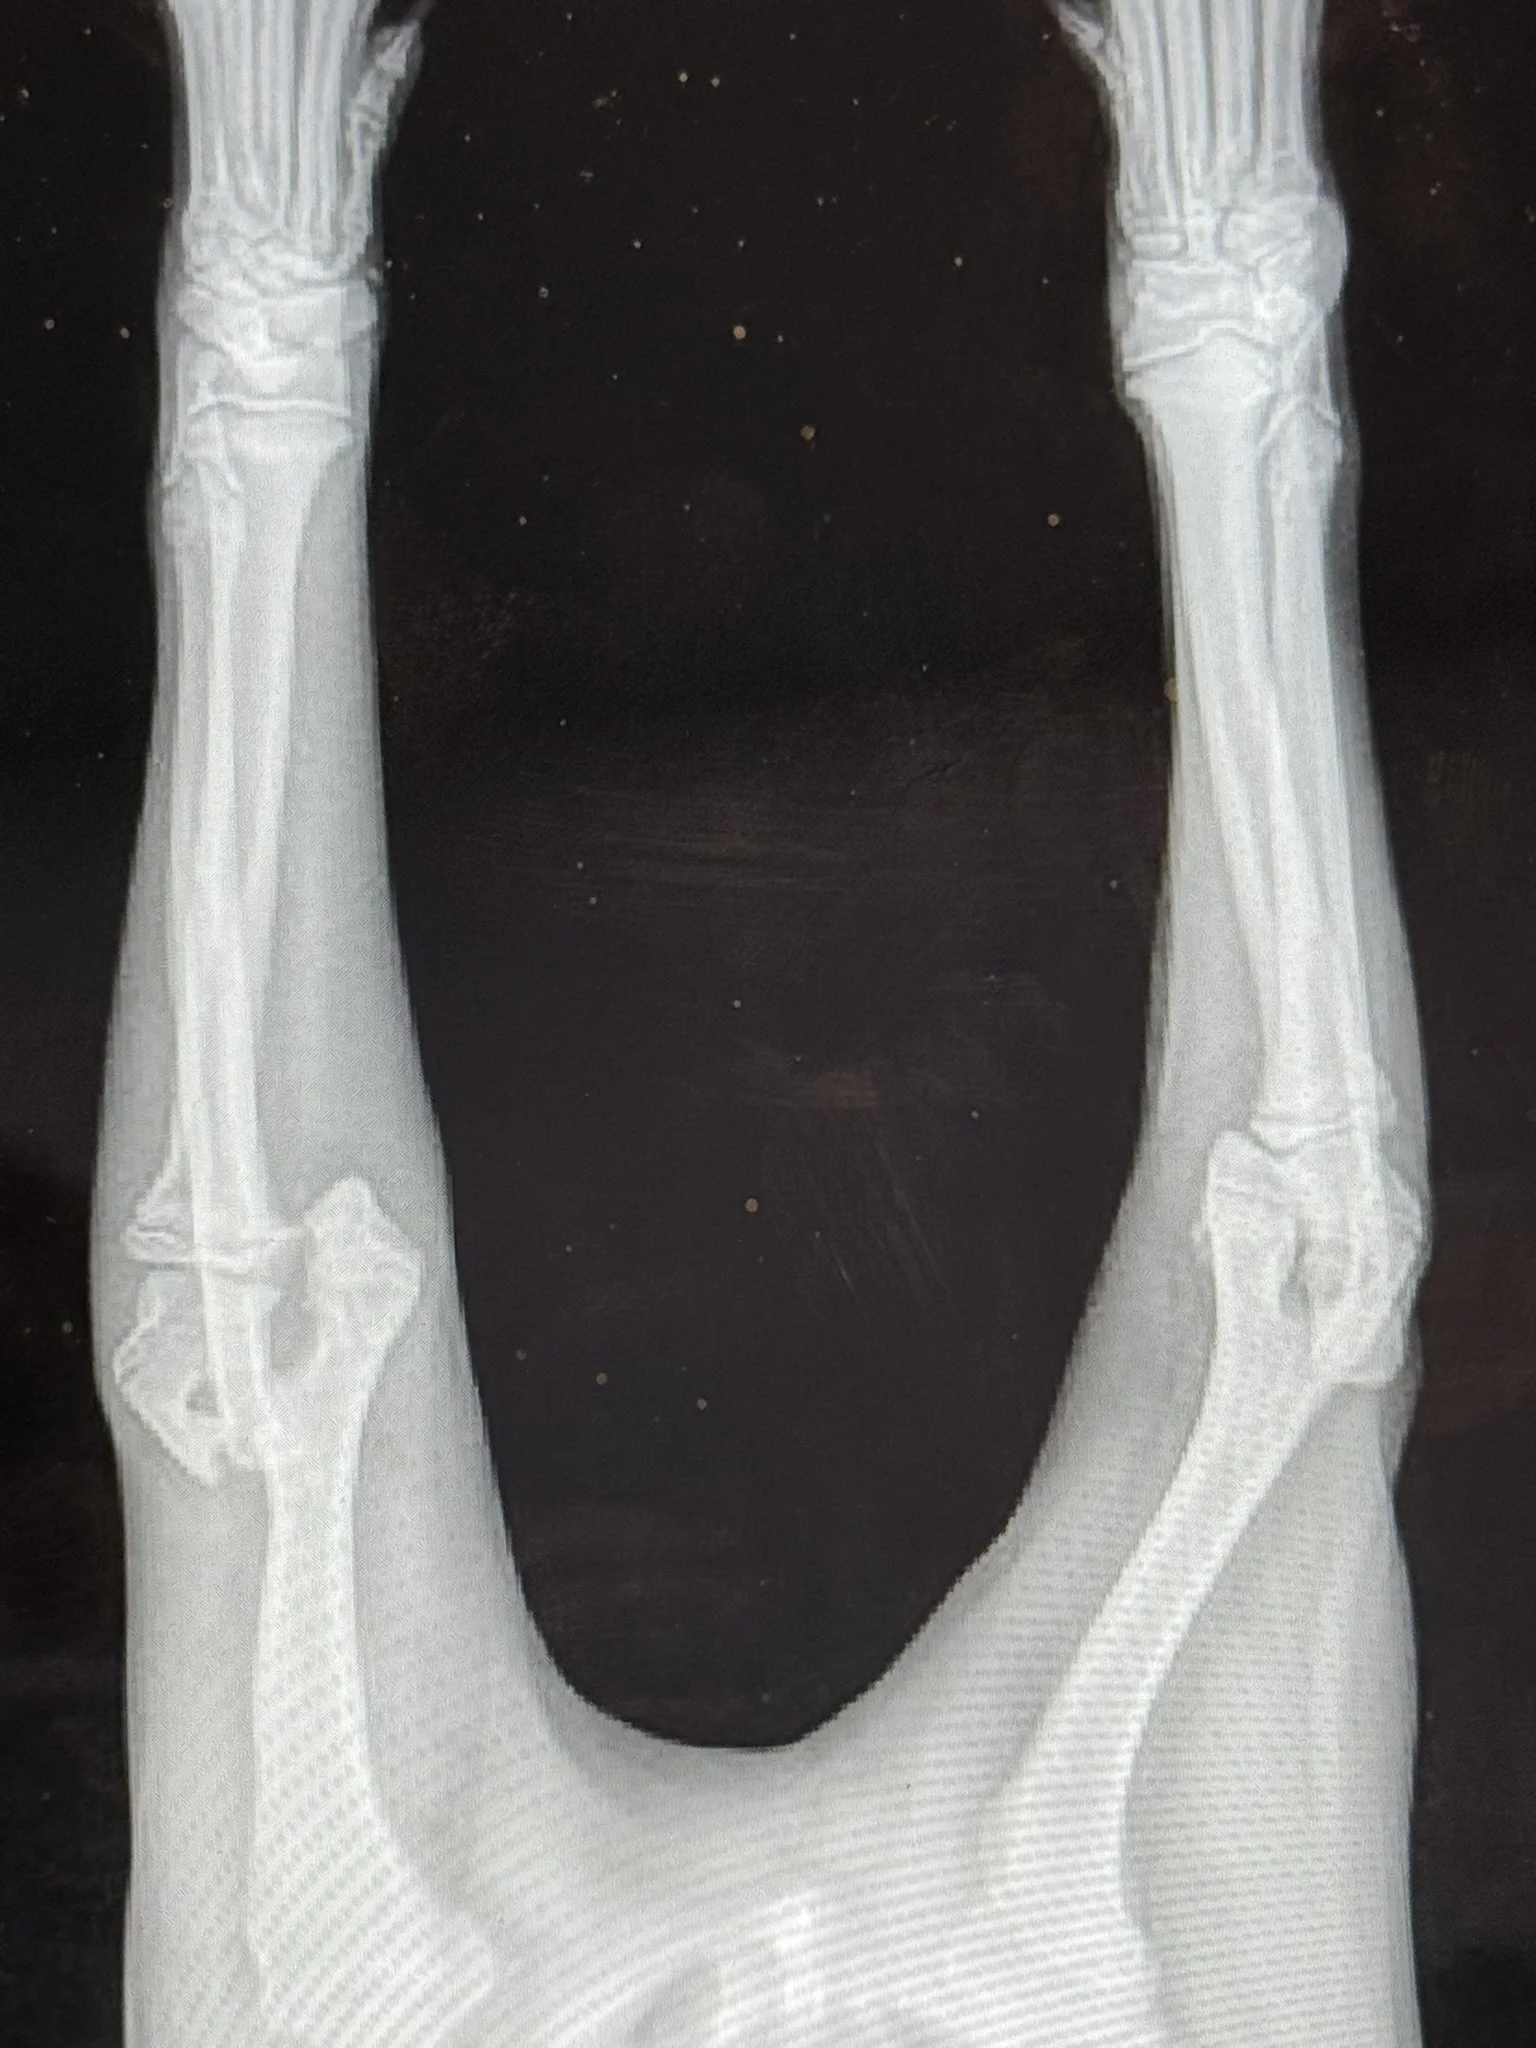

Frankie’s Friends helped Luna receive a fracture repair surgery.